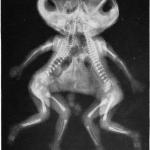

conjoined twins

A case report of 22-month-old conjoined twins evaluated and operated on last year at Massachusetts General Hospital was published in today’s New England Journal of Medicine (NEJM).

A ten month-old baby girl – called Dominique – born with two spines and four legs traveled from the Ivory Coast to Chicago to cross paths with a team of care givers who would successfully operate on her in a six-hour surgery.